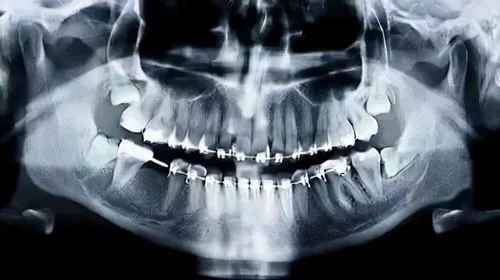

Комплексная диагностика.

Для детального исследования пораженной области задействуется томограф.